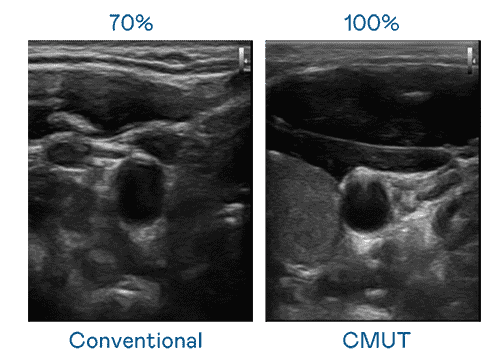

CMUT 技术是一种用电容式微机电元件来产生超音波讯号的技术。。与传统 PZT 压电式技术相比,,CMUT 频宽增加 30%,,,,更宽频的超音波讯号让影像解析度大幅提升,,,,是实现高影像品质医疗超音波扫描、、促进精准医疗发展的关键技术。。

大频宽带来超清晰影像

超音波影像的解析度高低,,,首先取决于探头能发出的讯号频宽。。人生就是博 CMUT 可提供高清晰的超音波讯号,,,,提供高频宽、、、、高灵敏度、、、影像纹理细节更高的超音波影像,,,,协助医护人员缩短影像判读时间及利用精准的医疗影像进行诊断。。。